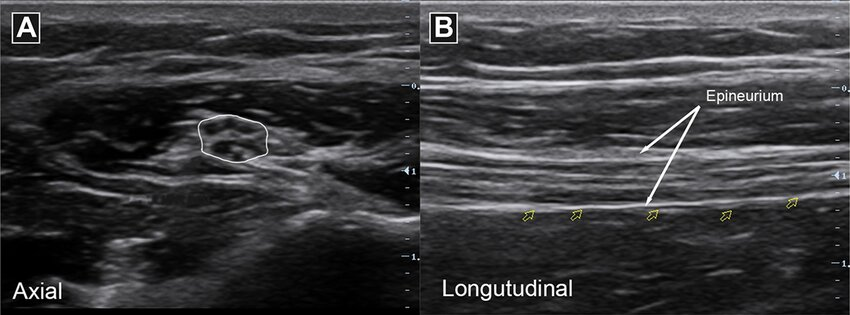

ultrasound: nerve

'Honey-comb' appearance in transverse view; 'train track' in longitudinal view